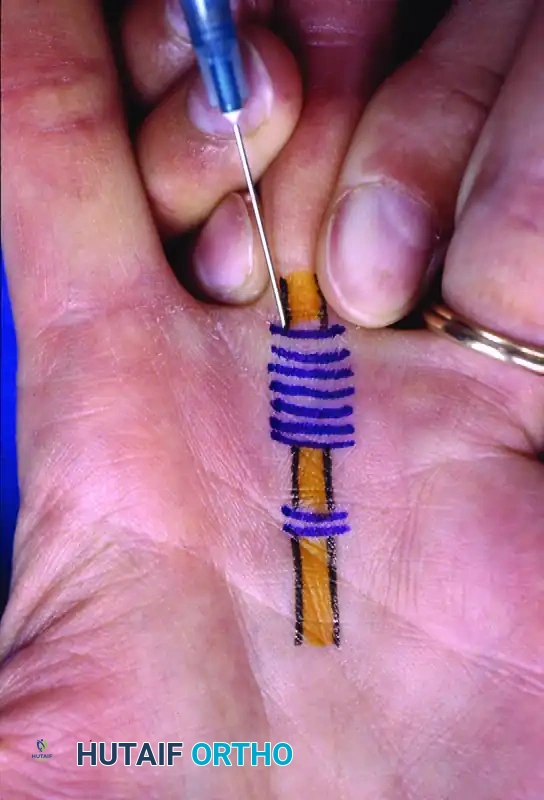

Figure: Percutaneous release of long finger A1 pulley. Metacarpophalangeal joint hyperextended and 19-gauge needle inserted just distal to the flexor crease. Skin markings indicate the path of flexor tendons.

- Stabilize the needle and use the sharp bevel to sweep and release the pulley from proximal to distal.

- A distinct loss of grating sensation as the pulley is cut indicates the completion of the release.

Figure: Needle stabilized and pulley released from proximal to distal.